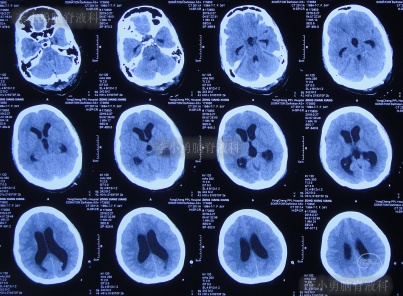

患者2019年2月初,因数次出现发作性黑蒙,2019年2月10日就诊于当地的河南省永城市某医院,查头颅CT未见明显异常(图-1);次日再查头颅核磁、颈椎核磁(图-2、图-3)后发现小脑扁桃体下疝畸形合并脊髓空洞。

图-2:2019年2月12日头颅核磁

图-3:2019年2月13日头颅核磁

但腰椎穿刺术后头痛仅短暂缓解1天左右,在该院继续治疗8天,仍间断头痛发热,间断给予腰穿治疗,化验脑脊液白细胞高,曾先后3次查头颅CT(图-5、图-6、图-7)均示脑室并未明显扩张。

图-5:2019年2月26日头颅CT

图-6:2019年2月27日头颅CT

图-7:2019年3月5日头颅CT